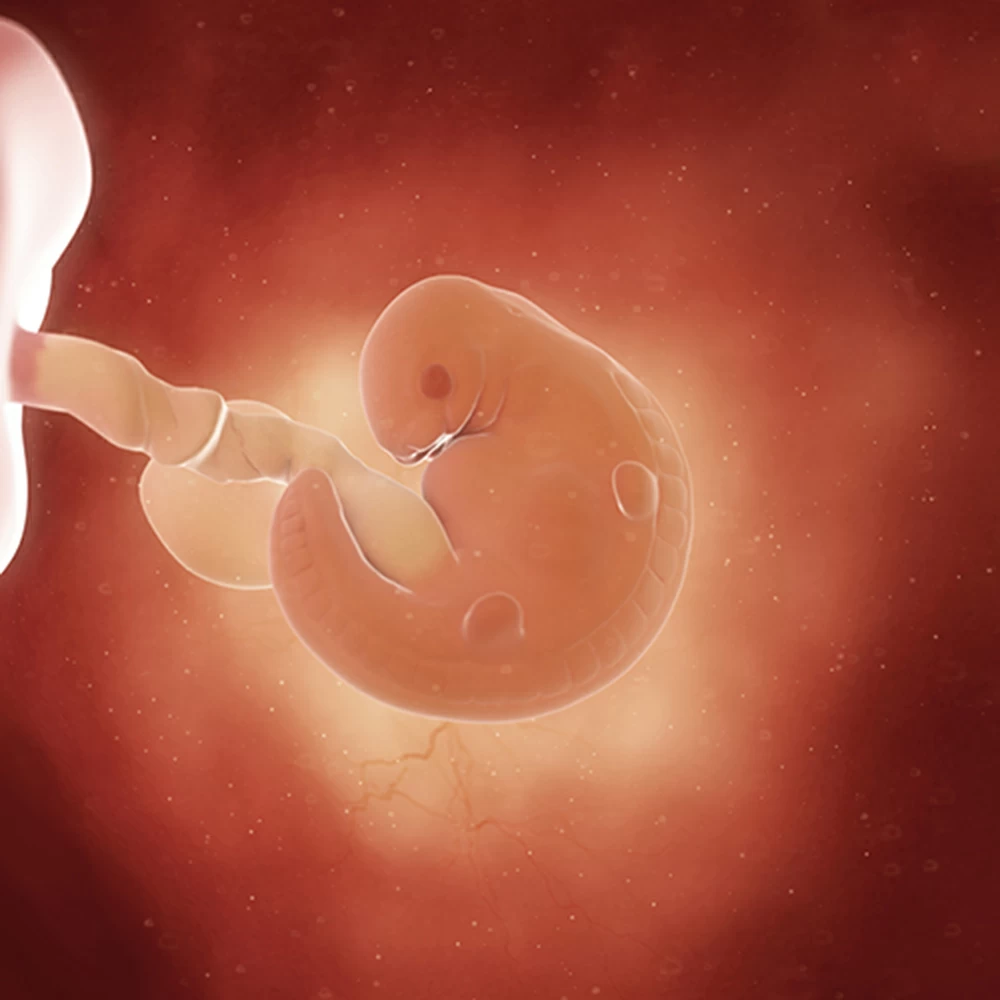

Дневник беременности